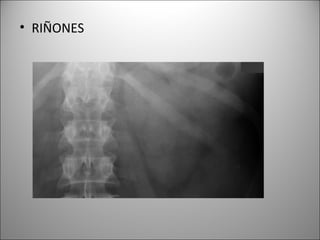

• RIÑONES